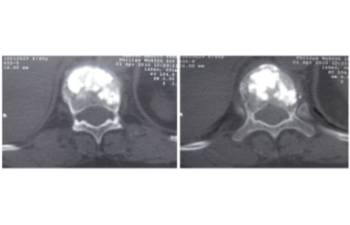

Comparació pre- i post-operatoria d’una cifopastia cementada

Dona, edat 55 anys, fractura aixafament dret de L2

Abans 1

Després 1

Abans 2

Després 2